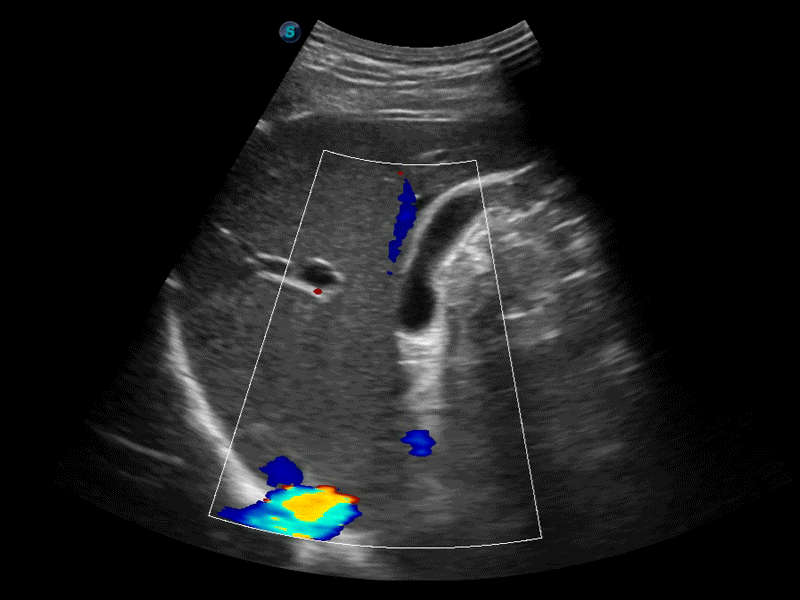

膀胱自动测量,一键式膀胱壁追踪和容量测量可有效提供更精确的轮廓和结果,不受膀胱形状和大小的影响。

自动优化快捷按键,实现成像参数自动优化,减少您调参花费的时间,可用于二维、彩色和频谱的一键优化。